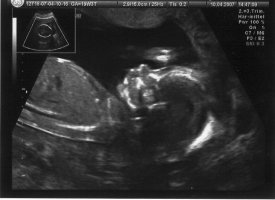

hier mal ein us-bildchen von gestern:

ha! so nun hier die überkreuzten beinchen in 3d. habs kleiner gekriegt. hoffe man erkennt noch was.